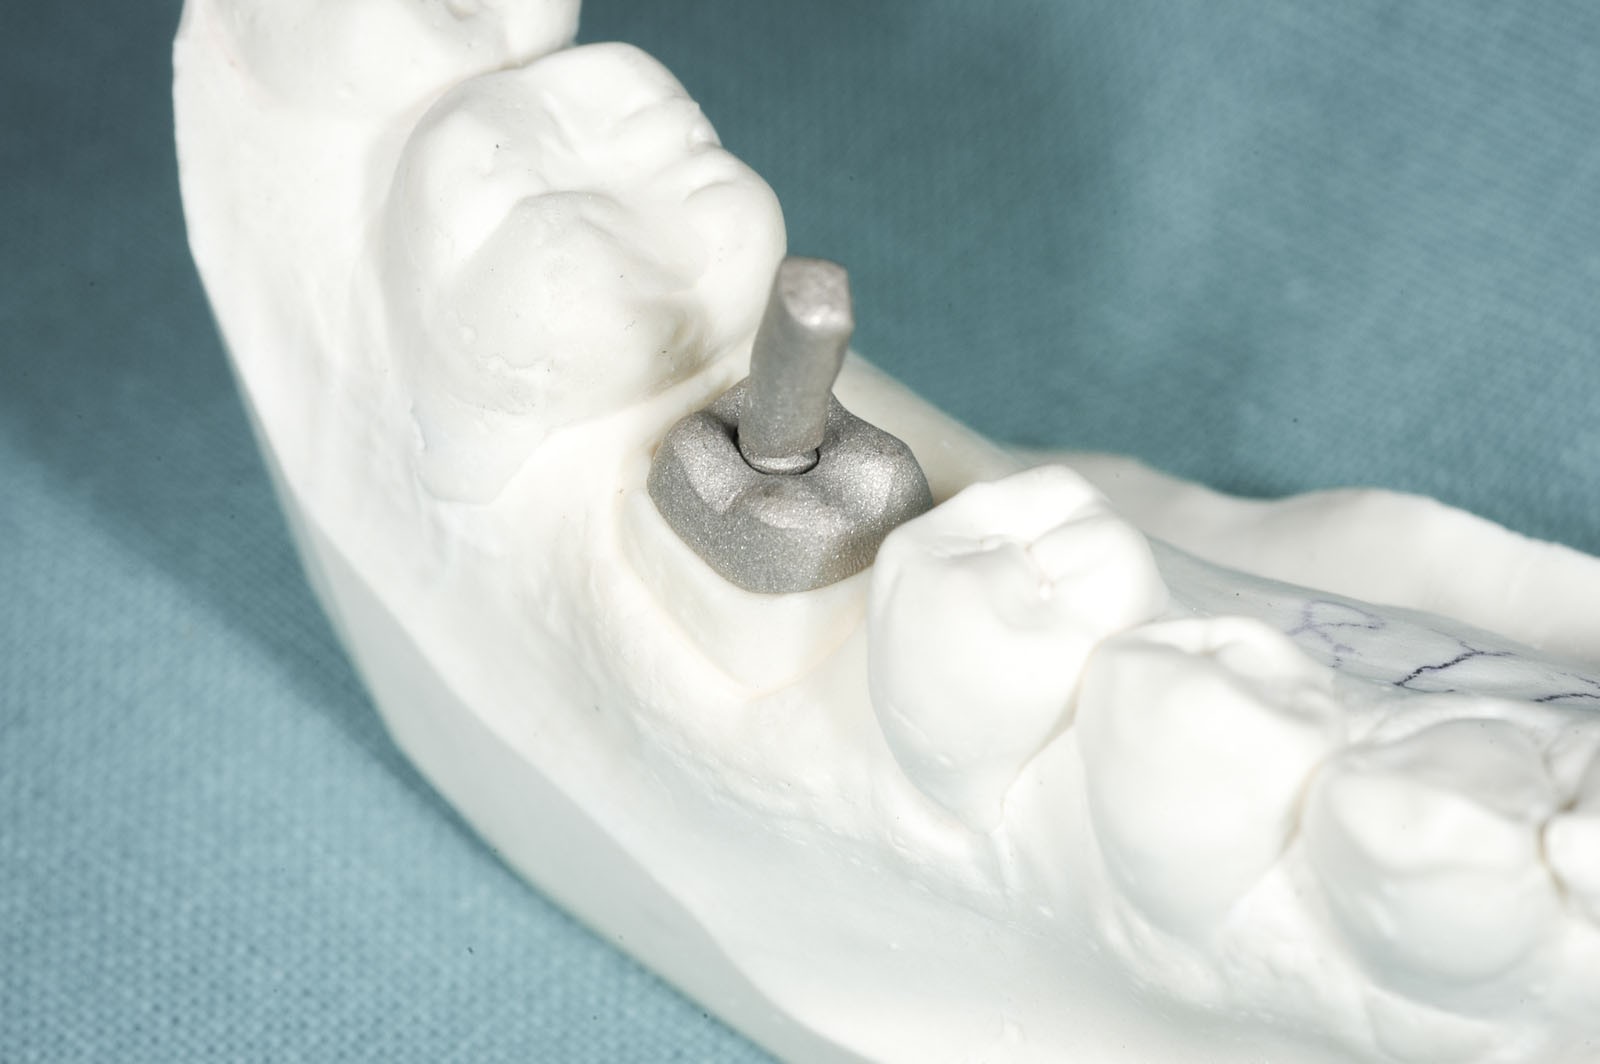

- Wkłady koronowo-korzeniowe – przeznaczone dla zębów po leczeniu kanałowym, których konstrukcja wymaga wzmocnienia ze względu na stopień jej uszkodzenia. Wkłady wykonywane są w laboratorium protetycznym lub w gabinecie stomatologicznym i montowane wewnątrz kanału korzeniowego zęba. Wkłady laboratoryjne to indywidualnie odlewane elementy ze stopów metali, podczas gdy w gabinecie używa się wykonanych z włókien syntetycznych.

Korona protetyczna ma za zadanie odbudować zniszczoną część naddziąsłową pojedynczego zęba. Przy dużej destrukcji twardych struktur zębowych często wykonanie korony powiązane jest z leczeniem endodontycznym. W sytuacji dużych zniszczeń części koronowej zęba i słabej retencji dla przyszłej korony protetycznej dodatkowo ząb powinien zostać wzmocniony wkładem koronowo-korzeniowym indywidualnie odlewanym ze stopów metalu w laboratorium lub gotowym, wykonanym z włókna szklanego. Wkład koronowo-korzeniowy cementuje się w kanale korzeniowym po prawidłowo przeprowadzonym leczeniu kanałowym.

Wkłady koronowo-korzeniowe to rusztowanie dla korony zęba. Ich zadaniem jest jego wzmocnienie. Stosuje się je w zębach leczonych kanałowo, w których doszło do dużego zniszczenia struktur korony zęba.

Wskazaniem do wykonania wkładów koronowo-korzeniowych jest wzmocnienie zęba leczonego kanałowo, w którym doszło do powstania dużego ubytku w jego części koronowej. Jeżeli ząb ma niewiele tkanek własnych lub są one uszkodzone, grozi to powstaniem naprężeń, w wyniku których może dojść do odłamania się jego ścian. Wkłady koronowo-korzeniowe zapobiegają uszkodzeniom mechanicznym zębów.